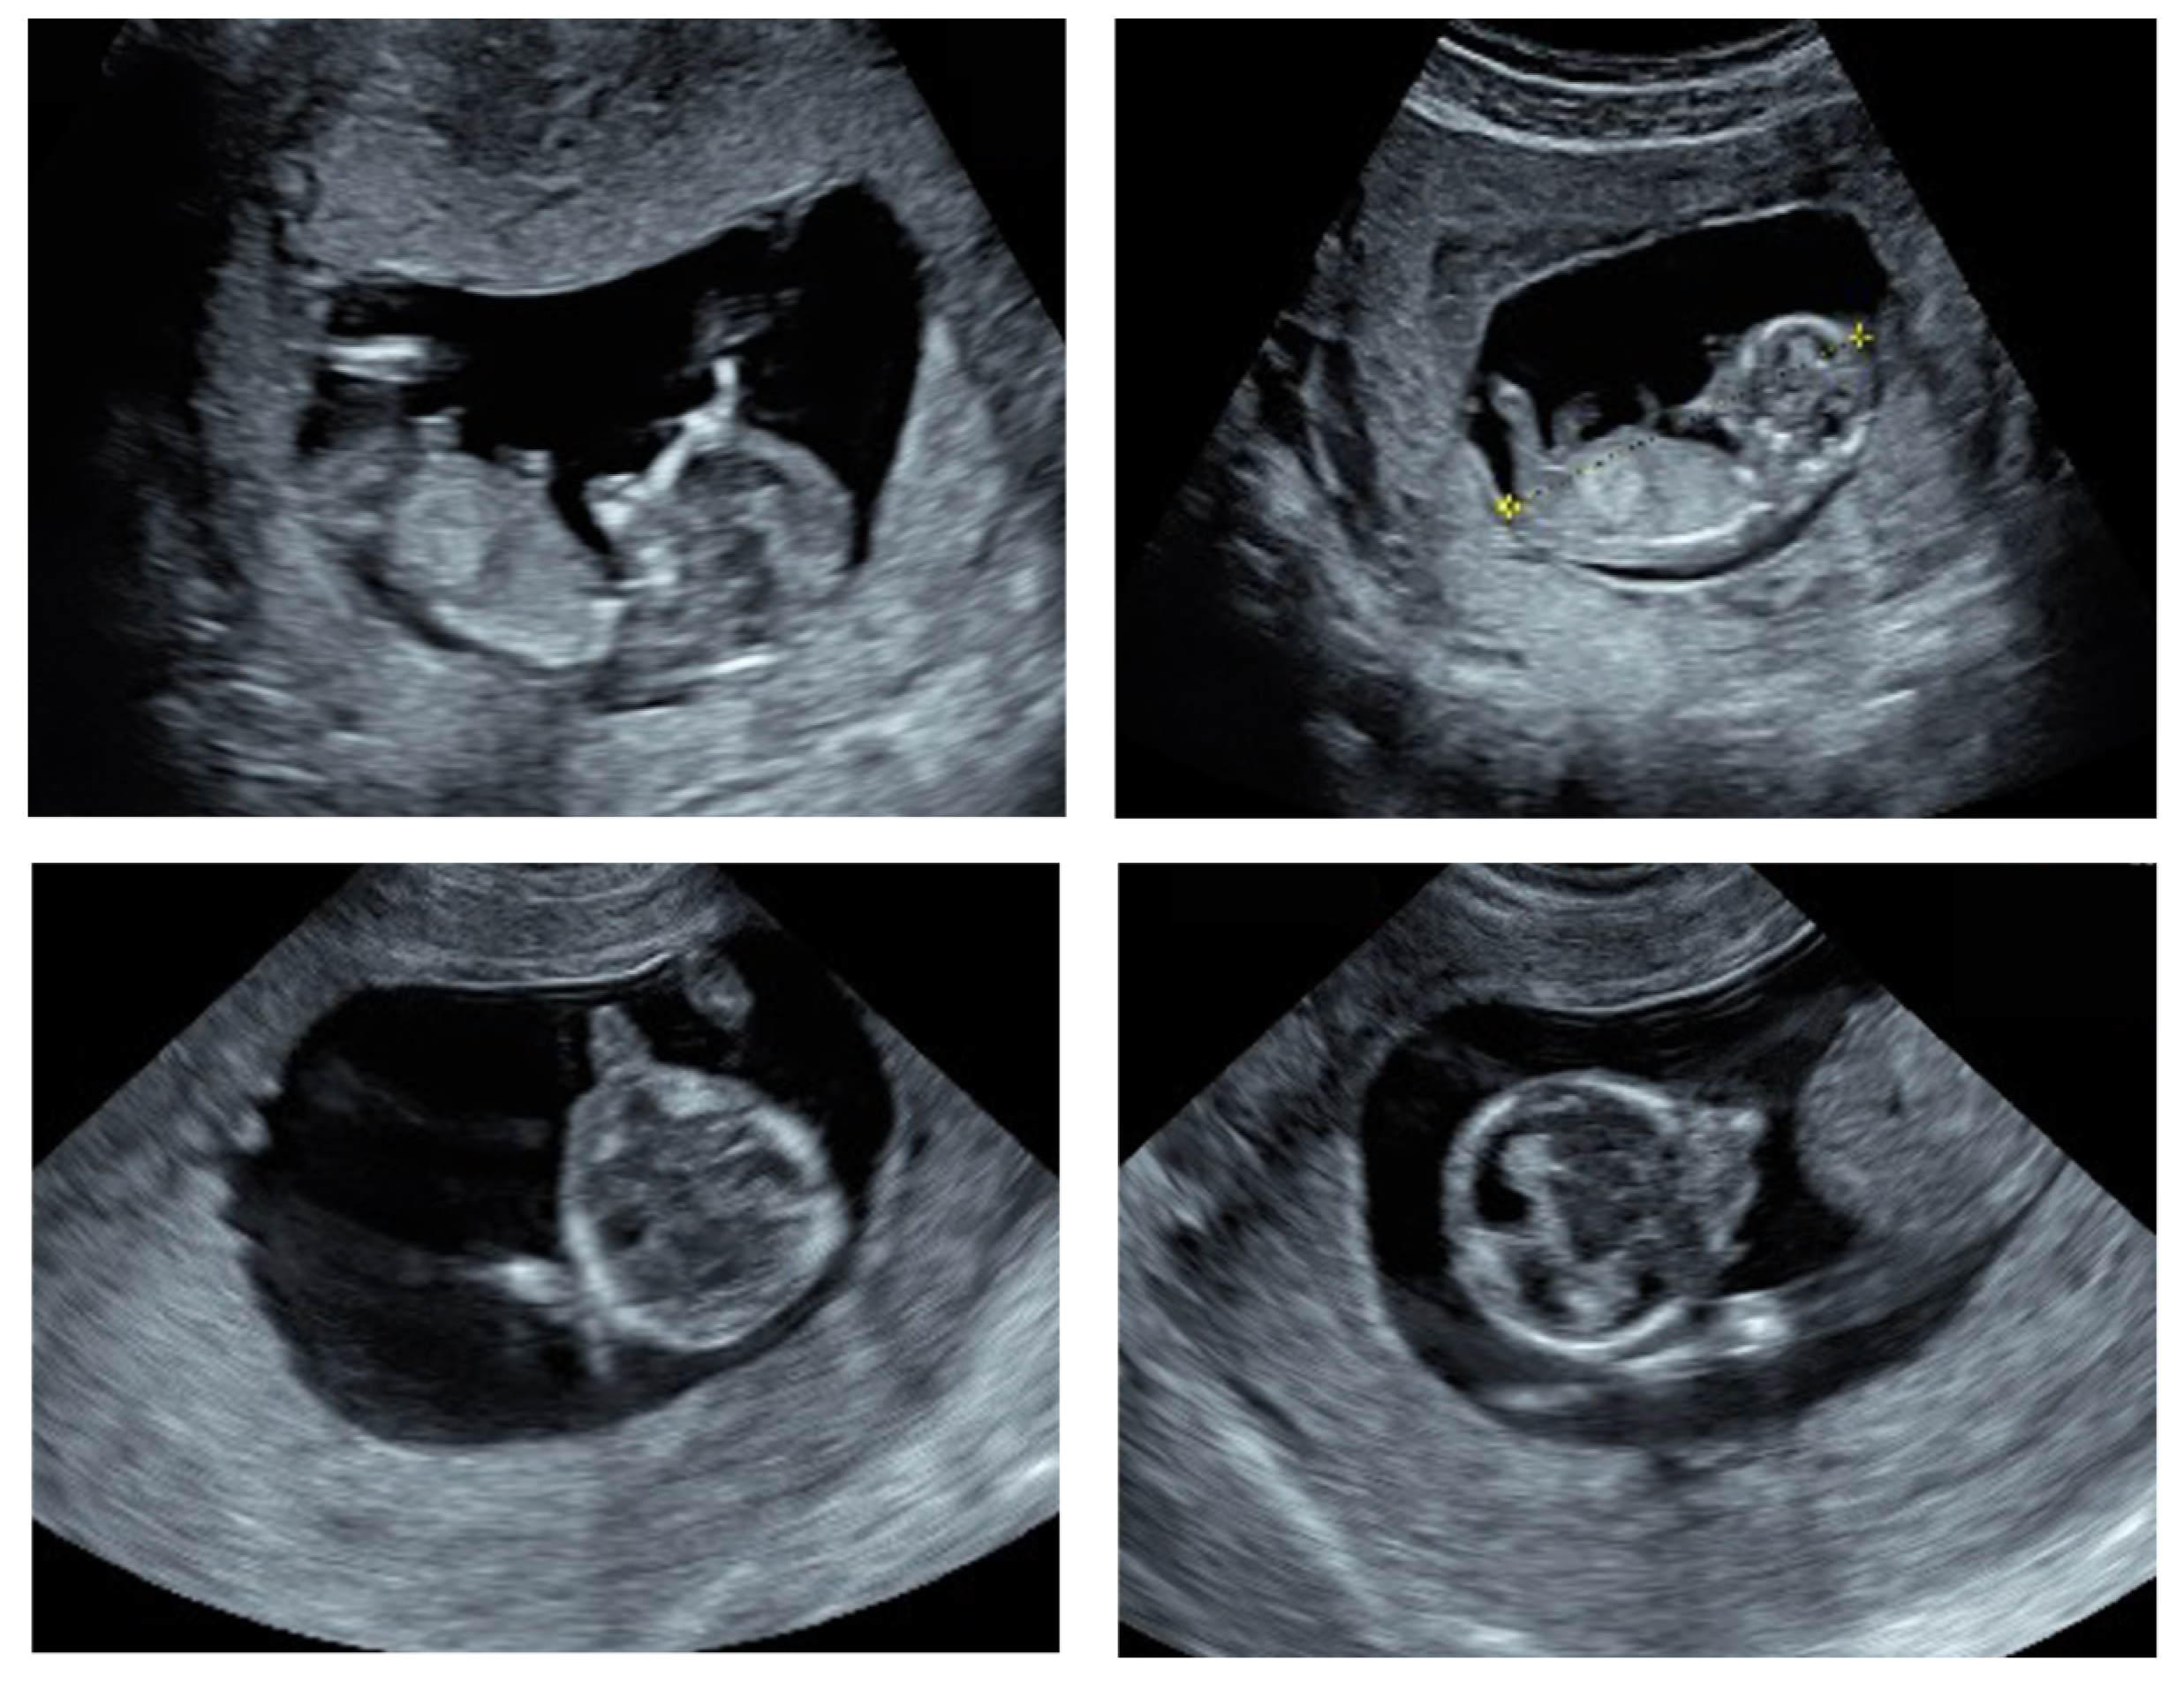

3.1. Clinical Features at Ultrasound and the Post Abortion Examinations